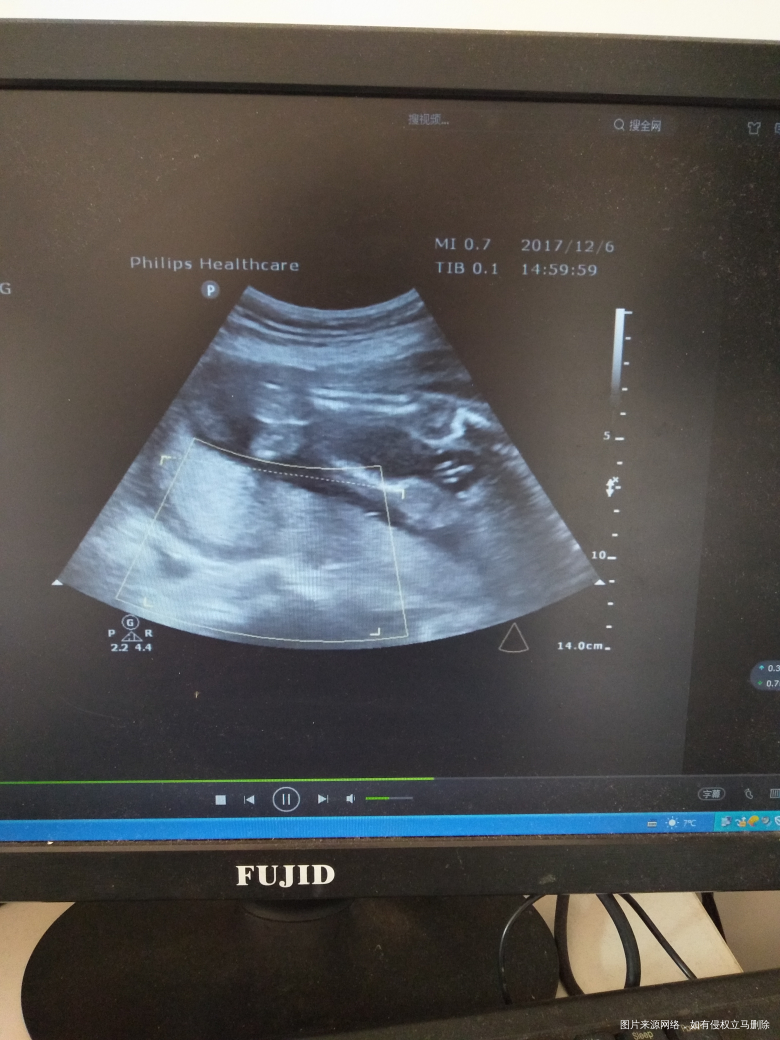

有宝宝的性器官图片 只是我还看不懂?有经验的宝妈可以帮我看一下

吗?

[大笑]下面那张像小鸡鸡

男孩吧

男孩

男宝吧,好清楚

像男孩

小鸡鸡好明显[大笑]